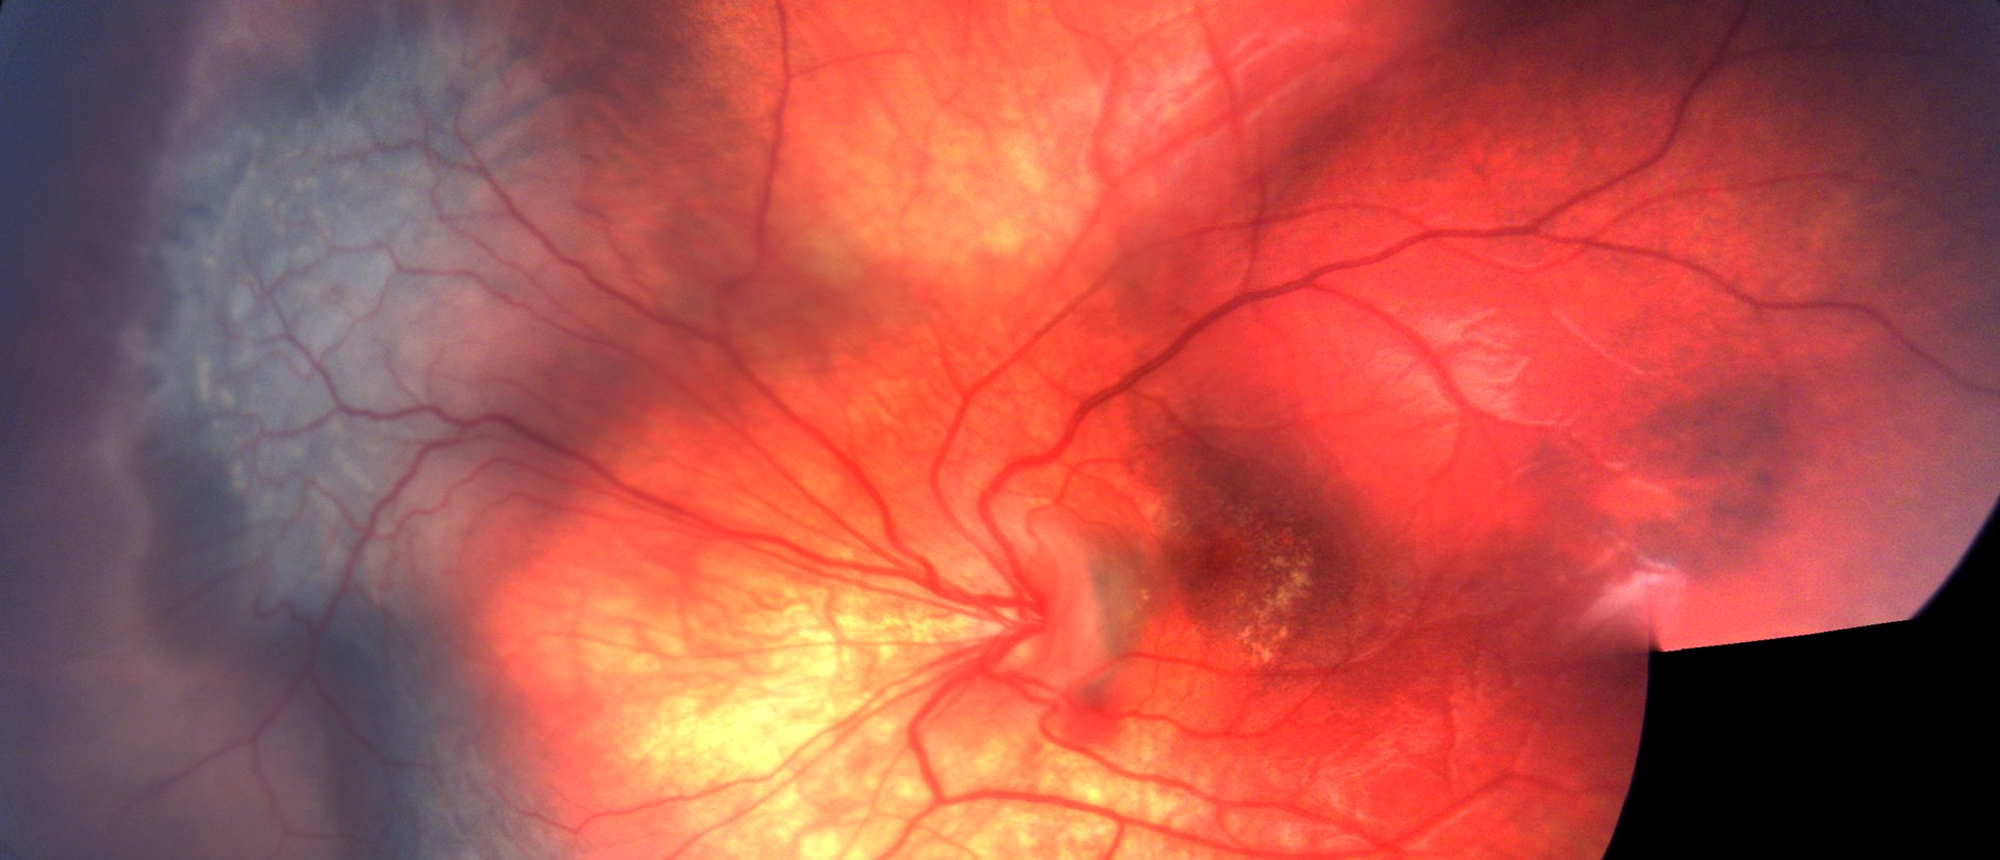

Acute Syphilitic Posterior Placoid Uveitis An adult patient presented to the Bascom Palmer emergency room for evaluation of five days of bilateral painless vision loss and floaters. On slit lamp examination he did not have any conjunctival injection or anterior chamber cell or flare. Dilated fundus…